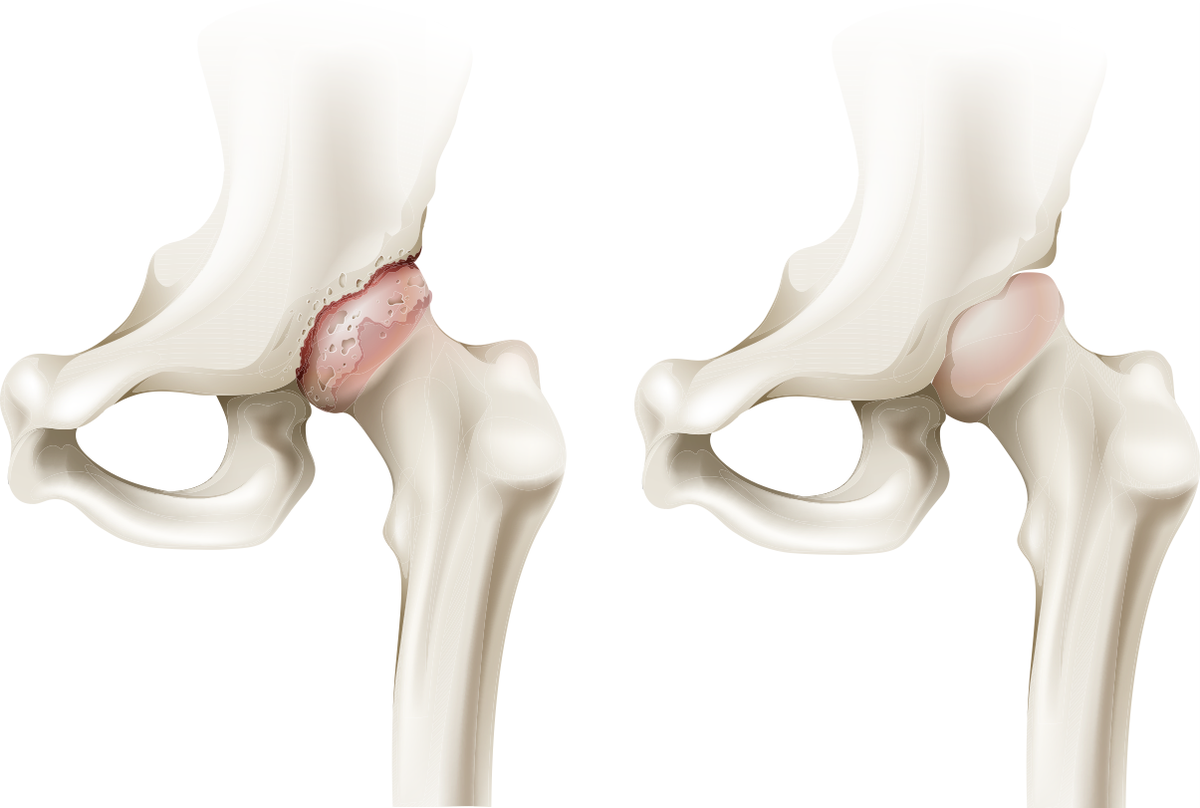

Ущемление бедренно-вертлужной впадины (FAI)/ущемление тазобедренного сустава: причины, симптомы и лечение

Эти процедуры могут помочь облегчить боль, но они не устранят структурные проблемы в ваших костях, поэтому ваши симптомы могут вернуться. Если вы пробовали лечить свои симптомы с помощью этих вариантов, но по-прежнему испытываете боль, вам может потребоваться хирургическое вмешательство для устранения проблем в вашем суставе.

Специалист может порекомендовать операцию, если у вас есть симптомы, которые причиняют боль или влияют на вашу способность участвовать в повседневной жизни.Целями хирургического вмешательства при ИА являются улучшение функции тазобедренного сустава, уменьшение болезненных симптомов и предотвращение или отсрочка необходимости замены тазобедренного сустава в будущем.

Существует несколько различных вариантов хирургического вмешательства в зависимости от того, что вызвало защемление бедра.